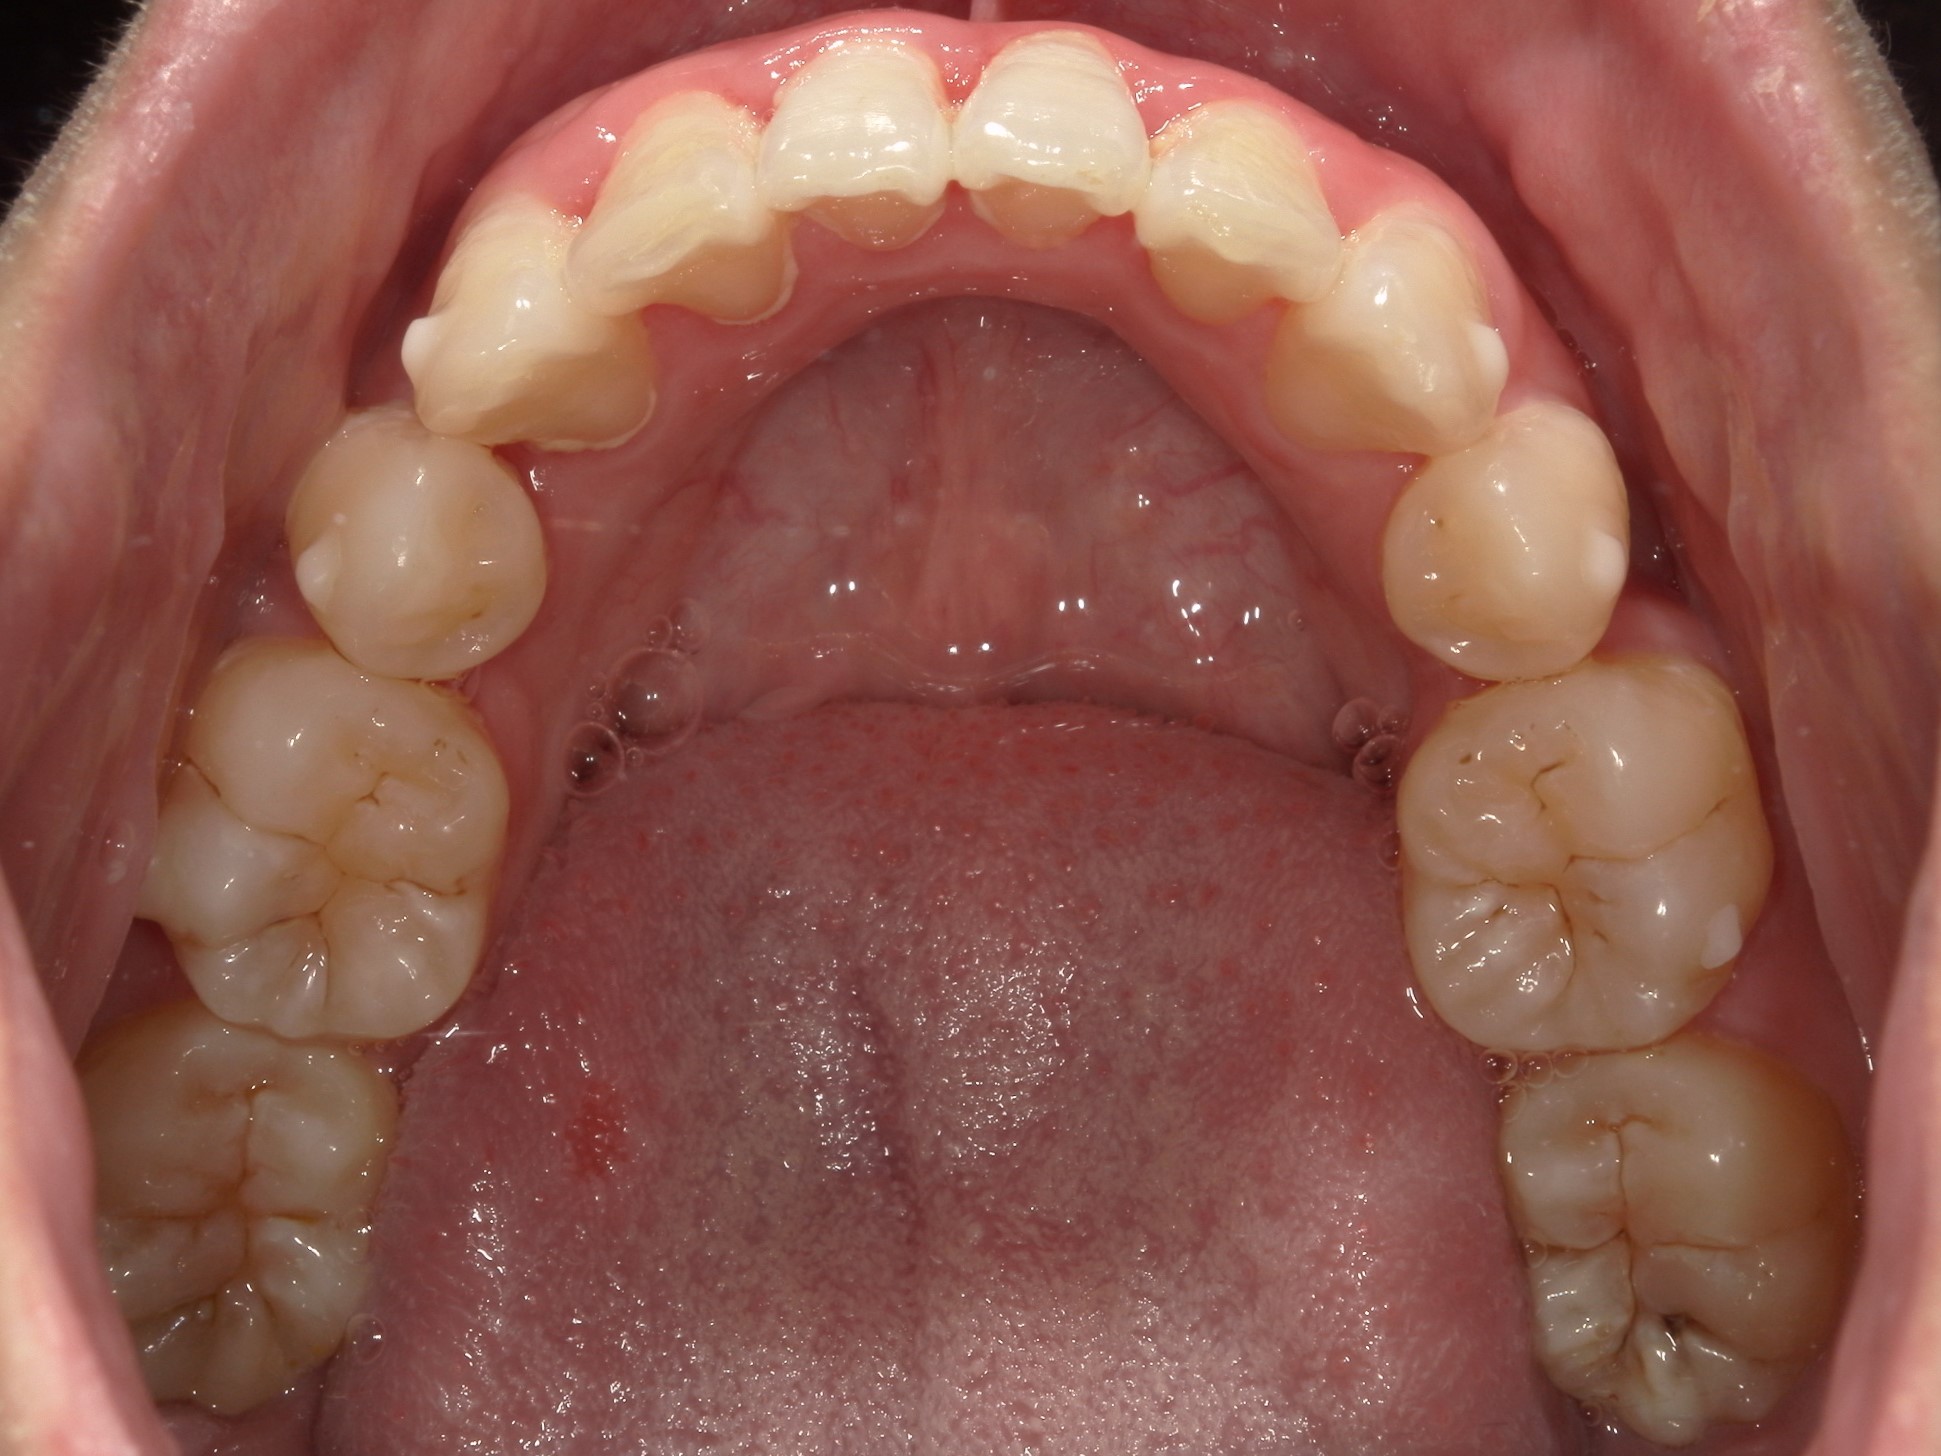

歯並びの乱れ(叢生)が気になる

| 年齢・性別 | – |

|---|---|

| 主訴 | 歯並びの乱れ(叢生)を気にされて来院された。咬み合わせや審美的な改善を希望されていました。 |

| 治療期間・回数 | 3年・28回 |

| 費用 | 840,000円 |